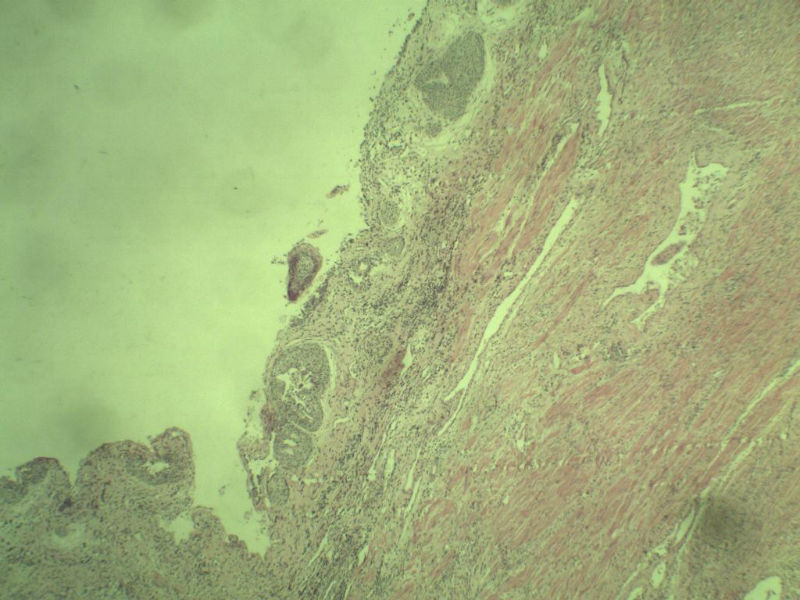

男 75岁 因排尿困难半年行前列腺切除术,体积 4 × 3 × 2.5 cm3,切面灰白,实性,质韧。请各位老师看看 有问题没? 谢谢了!

良性前列腺增生伴尿路上皮化生

前列腺增生症伴鳞化

前列腺增生伴尿路上皮鳞化及Brown巢形成,未见恶性。

呈巢上皮为尿道周围前列腺组织正常现象。尿路上皮-前列腺腺体过度。